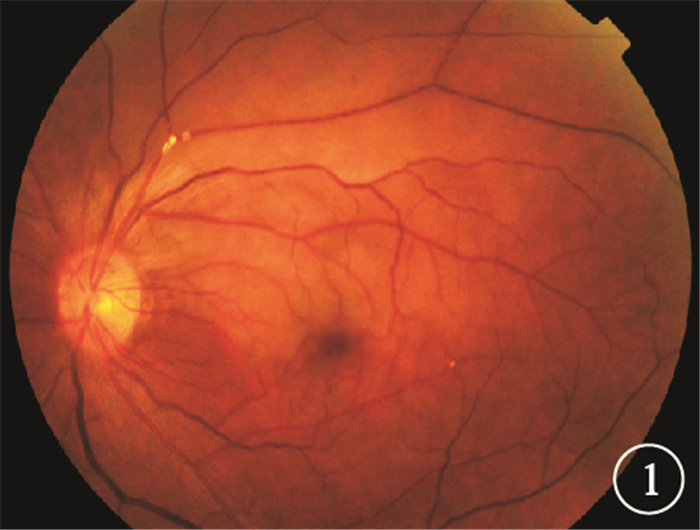

圖3

左眼治療5 d后彩色眼底像。視網膜顳上支動脈及靜脈管徑較前增粗,顳上支動脈主干分叉處的2個節段狀黃白色反光灶變小,其遠端小分支動脈閉塞區可見部分小分支動脈(白箭) 圖 4 左眼治療5 d后FFA像。4A.24.3 s,視網膜靜脈充盈,顳上支靜脈顳支仍無灌注;4B.27.9 s,顳上支靜脈顳支開始充盈;4C.38.9 s,顳上支靜脈顳支充盈完全

圖3

左眼治療5 d后彩色眼底像。視網膜顳上支動脈及靜脈管徑較前增粗,顳上支動脈主干分叉處的2個節段狀黃白色反光灶變小,其遠端小分支動脈閉塞區可見部分小分支動脈(白箭) 圖 4 左眼治療5 d后FFA像。4A.24.3 s,視網膜靜脈充盈,顳上支靜脈顳支仍無灌注;4B.27.9 s,顳上支靜脈顳支開始充盈;4C.38.9 s,顳上支靜脈顳支充盈完全

圖3

左眼治療5 d后彩色眼底像。視網膜顳上支動脈及靜脈管徑較前增粗,顳上支動脈主干分叉處的2個節段狀黃白色反光灶變小,其遠端小分支動脈閉塞區可見部分小分支動脈(白箭) 圖 4 左眼治療5 d后FFA像。4A.24.3 s,視網膜靜脈充盈,顳上支靜脈顳支仍無灌注;4B.27.9 s,顳上支靜脈顳支開始充盈;4C.38.9 s,顳上支靜脈顳支充盈完全

圖3

左眼治療5 d后彩色眼底像。視網膜顳上支動脈及靜脈管徑較前增粗,顳上支動脈主干分叉處的2個節段狀黃白色反光灶變小,其遠端小分支動脈閉塞區可見部分小分支動脈(白箭) 圖 4 左眼治療5 d后FFA像。4A.24.3 s,視網膜靜脈充盈,顳上支靜脈顳支仍無灌注;4B.27.9 s,顳上支靜脈顳支開始充盈;4C.38.9 s,顳上支靜脈顳支充盈完全